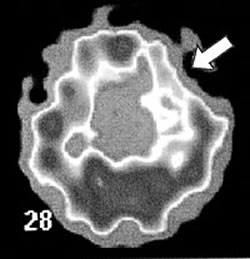

微量の放射線を発する物質を体内に入れて、外へ出る放射線を撮影する検査もあります(PET、SPECTなど)。脳の各部分の生理状態や代謝のようすが 外からわかり、てんかんがどこから始まるのかなどを調べることができます(図3)。

| 図3 SPECT(ECD)水平断 前頭葉てんかん |

| 発作間のないとき、(矢印)の部分は色が薄く血液が十分流れていないことがわかる。同部分がてんかんの起点と考えられる |